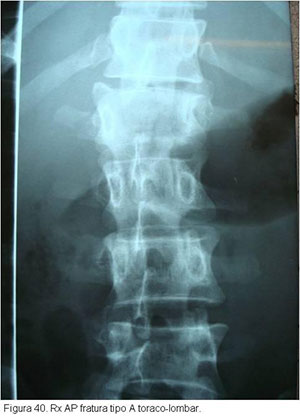

O tratamento seguirá o mesmo raciocínio discutido anteriormente, dependendo de quais estruturas estiverem lesadas. Particularidades da região toraco-lombar e lombar determinarão abordagens especificas caso a caso.(figuras 40, 41, 42 3, 44, 45)